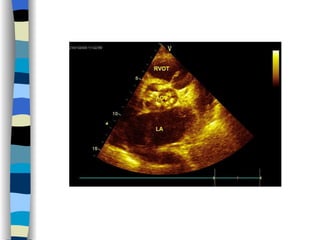

Echocardiography The most valuable technique for diagnosing MS, and determining its severity M-mode echo : Thickened, calcified leaflets open poorly, close slowly (EF slope ↓ ) The double peaks disappear Both leaflets move anteriorly during early diastole Two-dimensional echo: Fusion, thickening,  doming  of the valve leaflets, and poor leaflet separation in diastole;  mitral orifice area ↓

Doppler echo : Most accurate noninvasive technique for quantifying the severity of MS Spectrum Doppler: measure transvalvular gradient, MVA Color Doppler: display  high velocity color jet Provide other important information Cardiac chamber size (LA, RV) Left ventricular contractility Pulmonary arterial pressure Other coexisted valvular or congenital abnormalities  Mural thrombi